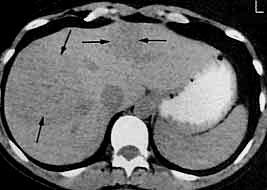

延迟2分钟显示病灶和肝实质密度一致.